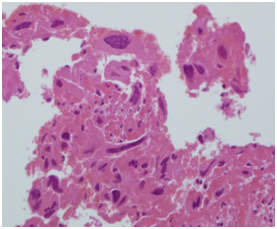

A specimen labeled as left frontoparietal hematoma - ? cavernoma from a 41 year old non-hypertensive female patient on ventilator was received for histopathologic examination. The patient was transferred from outside hospital to neurosurgical department of our hospital for craniotomy and evacuation of intracerebral hematoma. The clinoradiologic diagnosis was spontaneous intracerebral hematoma with intraventricular extension with normal ventricle, probably due to cavernoma. The microscopic examination of the specimen revealed extensive hemorrhage with peripherally placed mono-nucleated and multinucleated atypical cells. The mononucleotide cells were medium to large size with abundant cytoplasm and central large hyperchromatic nuclei. The multinucleated cells were large with abundant eosinophilic cytoplasm and hyperchromatic multinucleated bizarre nuclei. They were considered as cytotrophoblasts and syncytiotrophoblasts respectively (Figure 1-4). Immunohistochemistry showed that the atypical cells were CKAE1AE3 +, HCG+, GFAP-, CD31- and Vimentin- (Figure 5 to 10). A thin rim of GFAP positive glial tissue was seen in one fragment. Based on these findings, a diagnosis of metastatic choriocarcinoma was made. The patient survived the surgery and started recovering neurologically, but chose to go back to her own country for further management. So, we could not get any details of her obstetric history or previous medical illness.

Figure 1 Cytotrophoblasts.

Figure 2 Syncytiotophoblasts.

Figure 3 Cytotrophoblasts.

Figure 4 Syncytiotophoblasts.